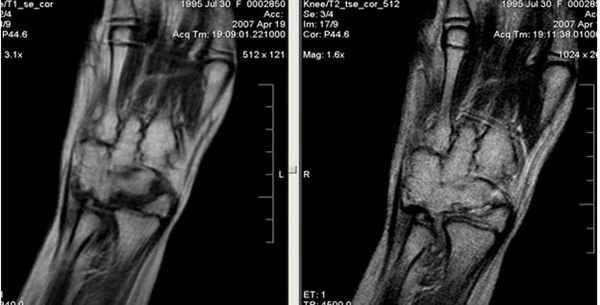

При клиническом обследовании больных с ушибами лучезапястного сустава и кисти, как правило, определяются болезненность при пальпации, увеличение объема окружающих мягких тканей, а объективно и рентгенологически изменения отсутствуют. Наиболее часто встречаются ушибы метаэпифиза лучевой и локтевой костей, а также полулунной и ладьевидной костей. Ушибы (контузионные поражения) кисти определяются только при МРТ-исследовании, особенно хорошо видно на программах с подавлением сигнала от жира. Морфологически ушиб кости проявляется нарушением целостности трабекул костной ткани с кровоизлиянием и отеком костного мозга. Однако, несмотря на повреждение трабекул костной ткани, рентгенологические исследования, включая КТ, не позволяют обнаружить патологические изменения.

Клинические проявления у пациента: боль и ограничение движений после падения на вытянутую руку 4 месяца назад.

Перелом ладьевидной кости с явлениями асептического некроза проксимального полюса и, связанного с ним, остеоартрита. Ладьевидный перелом обычно происходит из-за падения на вытянутую руку, которое приводит к гиперэкстензии лучезапястного сустава.

Аваскулярный (асептический) некроз нередко сопутствует переломам проксимальной части ладьевидной и переломам полулунной кости, а также неадекватно репонированным и иммобилизированным переломам этих костей. Основная причина – нарушение трофики участка кости при повреждении питающих артерий.

Методом выбора в диагностике и стадировании остеонекроза костей кисти является МРТ.